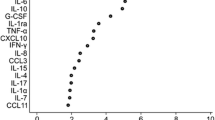

The number of IL-17 and IFN-γ SFCs are summarized in Table 3. Significant differences between groups are displayed in Fig. 3.

IL-17 (a) and IFN-γ (b) spot-forming cells. Boxes contain values from the first to the third quartile, lines inside the box indicate median values, and endpoints of vertical lines represent minimum and maximum values, and • represent outliners. Circles indicate statistically significant differences from the healthy group (oooo p < 0.0001, ooo p < 0.005, oo p < 0.01, o p < 0.05). Number sign indicates statistically significant differences between idiopathic epilepsy (#p < 0.05) and other groups. SFCs: spot-forming cells, IL-17: interleukin-17, IFN-γ: interferon gamma, SRMA A: steroid-responsive meningitis-arteritis in acute stage, SRMA T: SRMA patients under treatment, MUO: meningoencephalitis of unknown origin, IVDH: intervertebral disc herniation